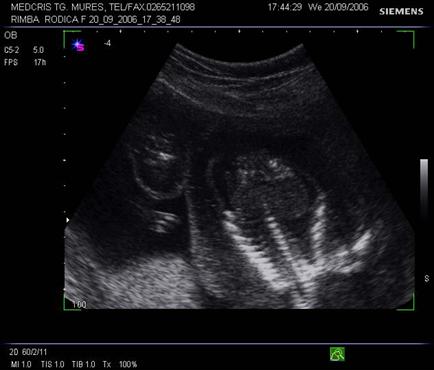

Fig. nr. 241. Fat cu hidrops nonimun , cu insuficienta cardiaca si bradicardie , la 28 sapt., se remarca hepatomegalia ( sageata ) si dilatatia venei cave inferioare

( doua sageti )

Fig. nr. 242. Aceeati sarcina ca in figura precedenta, se remarca lichidul pericardic si bilateral cel pleural, in sectiune transversala la nivel toracic fetal.